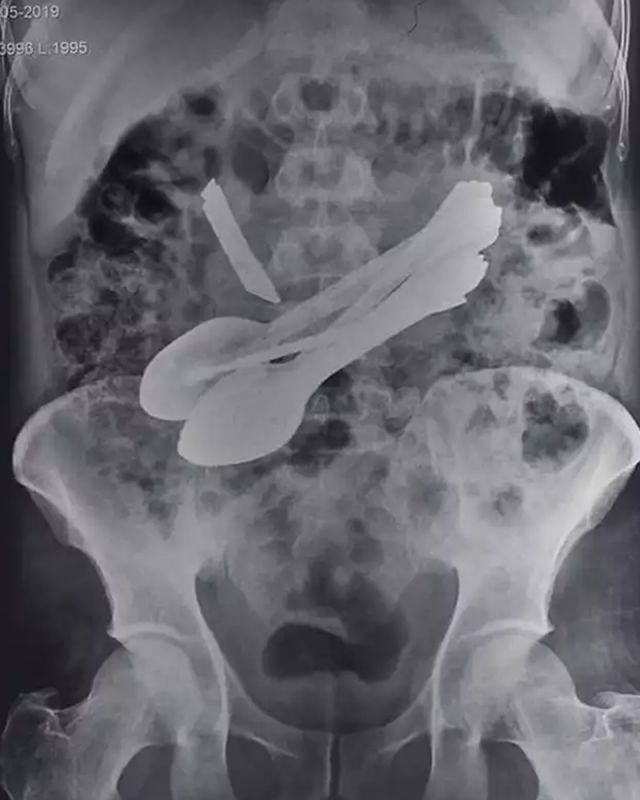

ਸੁੰਦਰਨਗਰ- ਹਿਮਾਚਲ ਪ੍ਰਦੇਸ਼ ਦੇ ਮੰਡੀ ਵਿਚ ਇਕ ਅਨੋਖਾ ਮਾਮਲਾ ਸਾਹਮਣੇ ਆਇਆ ਹੈ। ਜਿੱਥੇ ਇਕ ਵਿਅਕਤੀ ਦੇ ਪੇਟ ਵਿਚੋਂ ਕਈ ਚਮਚੇ, ਟੂਥਬਰੱਸ਼, ਚਾਕੂ, ਦਰਵਾਜ਼ੇ ਦੀ ਕੁੰਡੀ ਅਤੇ ਸਕਰੂਅ ਵਗੈਰਾ ਨਿਕਲੇ। ਮਰੀਜ਼ ਦੀ ਸਰਜਰੀ ਕਰਨ ਵਾਲੇ ਡਾਕਟਰ ਵੀ ਇਹ ਸਭ ਦੇਖ ਕੇ ਹੈਰਾਨ। 35 ਸਾਲਾ ਇਸ ਵਿਅਕਤੀ ਨੂੰ ਢਿੱਡ ਵਿਚ ਦਰਦ ਹੋਣ ਤੋਂ ਬਾਅਦ ਹਸਪਤਾਲ ਲਿਆਂਦਾ ਗਿਆ ਸੀ ਪਰ ਜਦੋਂ ਡਾਕਟਰਾਂ ਨੇ ਉਸ ਦਾ ਐਕਸਰਾ ਕੀਤਾ ਤਾਂ ਉਹ ਹੈਰਾਨ ਰਹਿ ਗਏ।

ਜਿਸ ਵਿਚ ਚਮਚੇ ਅਤੇ ਚਾਕੂ ਸਾਫ਼ ਨਜ਼ਰ ਆ ਰਹੇ ਸਨ। ਇਸ ਤੋਂ ਬਾਅਦ ਡਾਕਟਰਾਂ ਨੇ ਕਰੀਬ ਚਾਰ ਘੰਟੇ ਤੱਕ ਮਰੀਜ਼ ਦੀ ਸਰਜਰੀ ਕੀਤੀ ਤਾਂ ਉਸ ਦੇ ਢਿੱਡ ਵਿਚੋਂ ਇਕ ਚਾਕੂ, 8 ਚਮਚੇ, ਦੋ ਸਕਰੂ, ਦੋ ਟੂਥ ਬਰੱਸ਼ ਅਤੇ ਇਕ ਸਟੀਲ ਦਾ ਟੁਕੜਾ ਨਿਕਲਿਆ। ਮਰੀਜ਼ ਦੀ ਸਰਜਰੀ ਕਰਨ ਵਾਲੇ ਡਾਕਟਰ ਸੂਰਜ ਭਾਰਦਵਾਜ ਨੇ ਦੱਸਿਆ ਕਿ ਇਲਾਜ ਦੌਰਾਨ ਮਰੀਜ਼ ਦੇ ਢਿੱਡ 'ਤੇ ਚਾਕੂ ਦੀ ਨੋਕ ਵਰਗਾ ਕੁੱਝ ਦਿਖਾਈ ਦਿੱਤਾ, ਜਿਸ ਤੋਂ ਮਰੀਜ਼ ਦਾ ਐਕਸਰਾ ਕੀਤਾ ਗਿਆ ਜੋ ਹੈਰਾਨ ਕਰਨ ਵਾਲਾ ਸੀ।